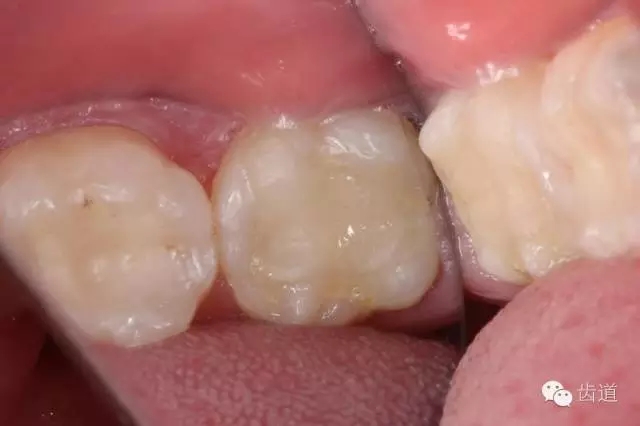

10. 術(shù)后即刻口內(nèi)照片

檢查:術(shù)后半年回訪,37牙體及合面嵌體未見缺損及裂紋,邊緣密合,未探及繼發(fā)齲,探痛-,叩痛-,松動-,冷水刺激痛-,未探及牙周袋及附著喪失,牙齦無紅腫,X線片檢查示根尖周膜連續(xù)性恢復(fù),根尖周透射影消失。

1. 術(shù)后半年口內(nèi)照片